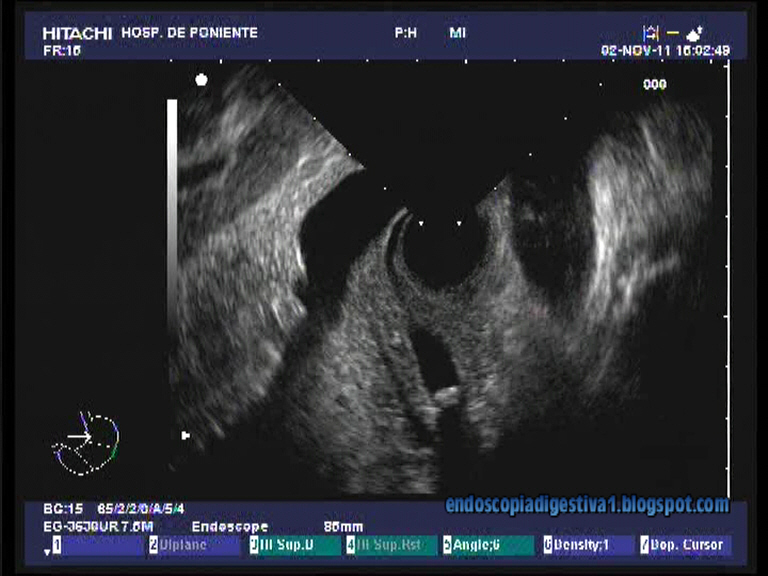

La ultrasonografía endoscópica (USE), por fin, se está difundiendo en muchos centros hospitalarios de nuestro país. Aunque es una técnica con una curva de aprendizaje relativamente larga, tiene como grandes ventajas que sus complicaciones son similares a las de una gastroscopia y la grandes posibilidades diagnósticas (sobre todo) y terapéuticas. Una de las indicaciones clásicas, donde la técmica tiene una gran rentabilidad diagnóstica (S y E cercanas al 100 %), es la coledocolitiasis, incluso aquellas < 5 mm como el caso que aquí se presenta. Cuando se compara con la CPRM (colangiopancreatografía por RMN) la S y E es algo mayor que ésta. Además suele ser bastante sencilla y rápida de realizar para descartar esta patología. Los dos instrumentos (radial y sectorial) son válidos, aunque es cierto que la USE radial es bastante mas sencilla de realizar dado que las imágenes son mas familiares en la interpretación anatómica.